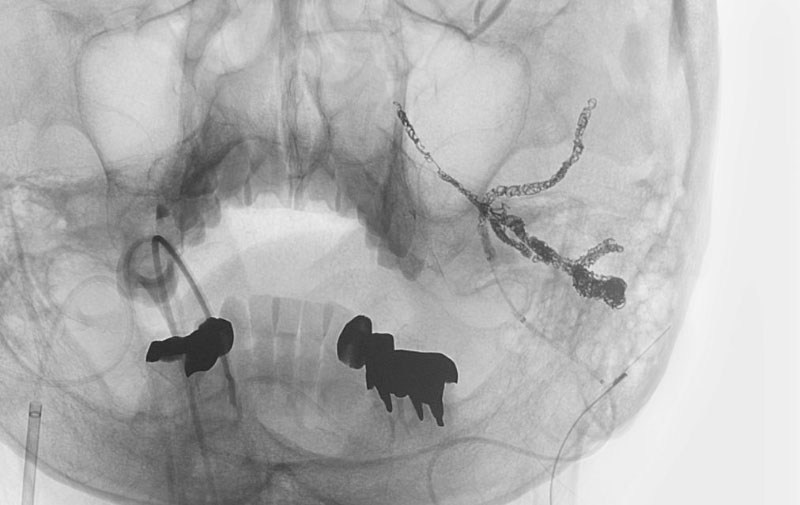

No.1203 手術前